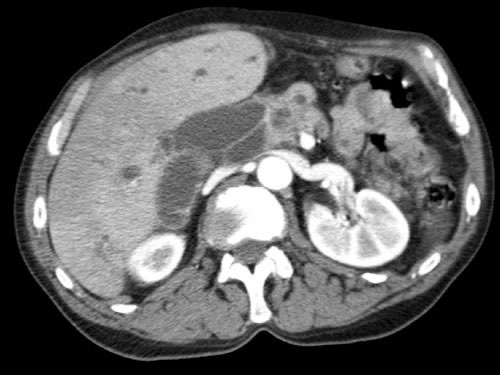

Các hình ảnh axial của cùng bệnh nhân có chú thích.

Hình MIP mặt phẳng đứng ngang này cho thấy một động mạch gan phải thay thế xuất phát từ phía phải của SMA (mũi tên vàng trong A).

Động mạch này đi qua vùng lân cận đầu tụy.

Hình CT axial cho thấy đường đi của động mạch gan phải thay thế phía sau tĩnh mạch cửa (đầu mũi tên vàng) và động mạch gan trái nguyên bản đi phía trước tĩnh mạch cửa (đầu mũi tên xanh lá).

Các hình ảnh mặt phẳng đứng ngang của một bệnh nhân có khối u ở đầu tụy và động mạch gan phải phụ thêm.

Lưu ý sự áp sát của động mạch phụ thêm bởi khối u.